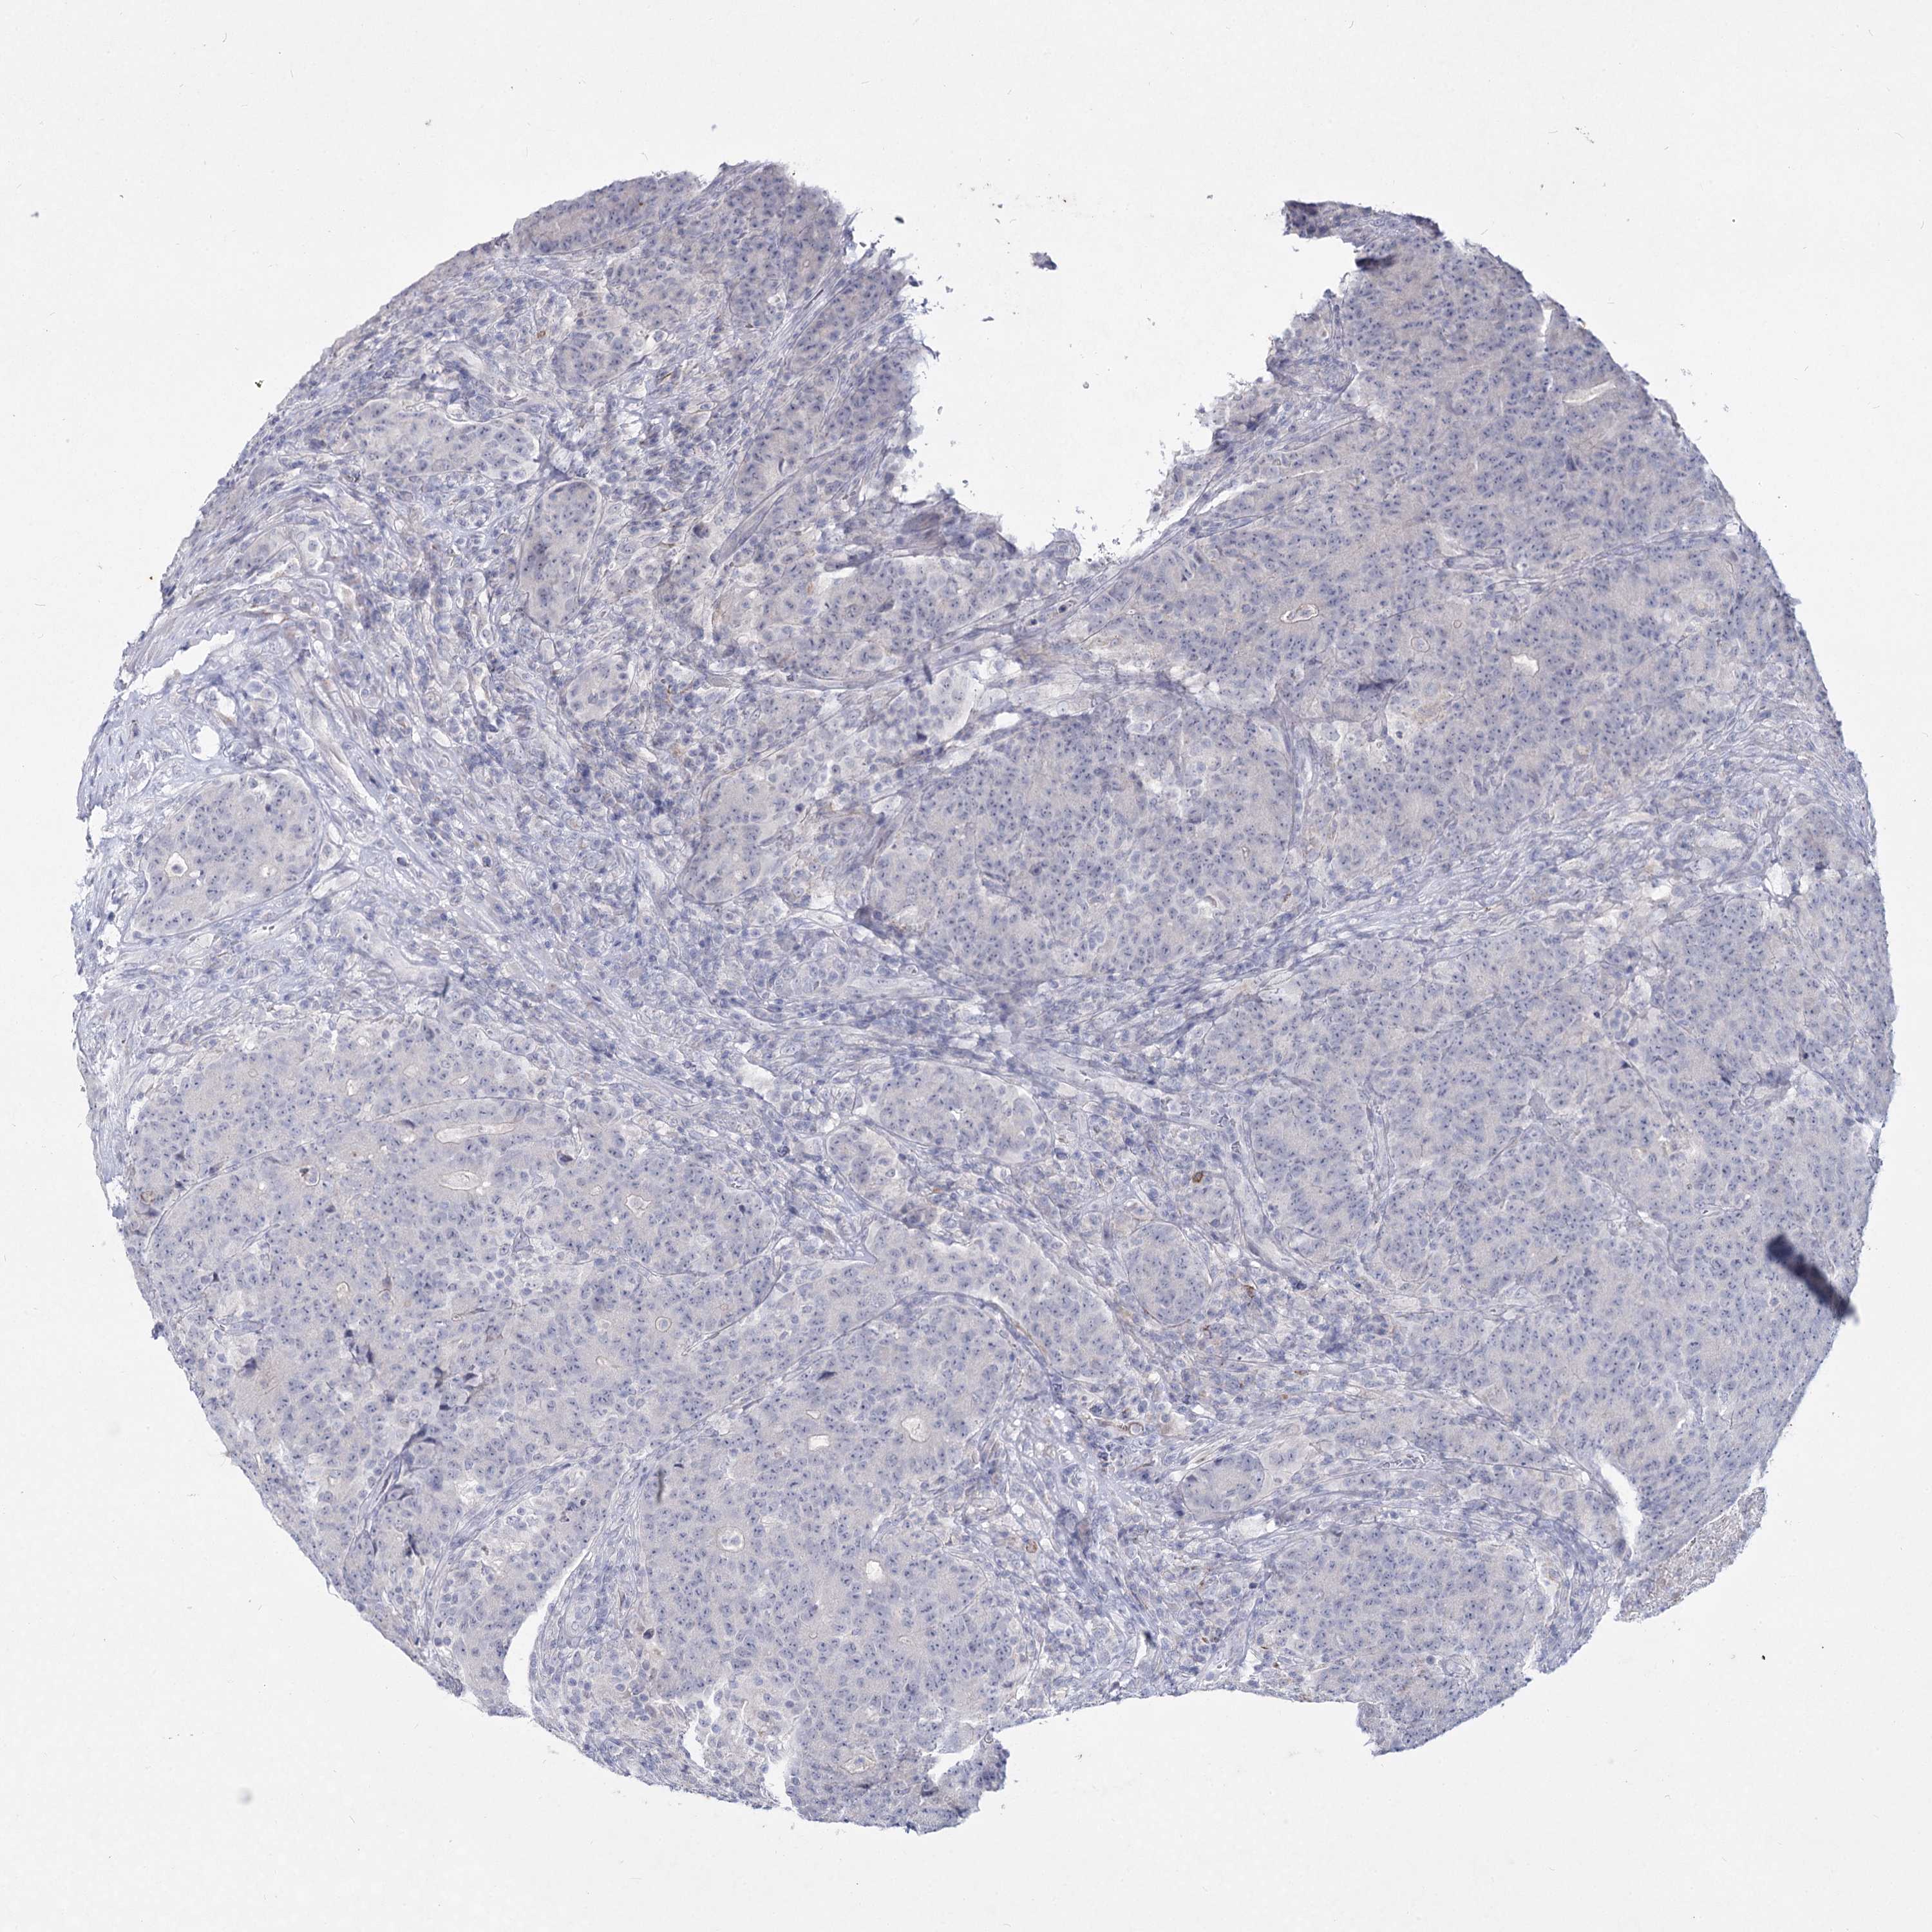

CANCER COLORECTAL CANCER Show tissue menu

Colorectal cancer

Human cancer

Colon adenocarcinoma

Rectum adenocarcinoma